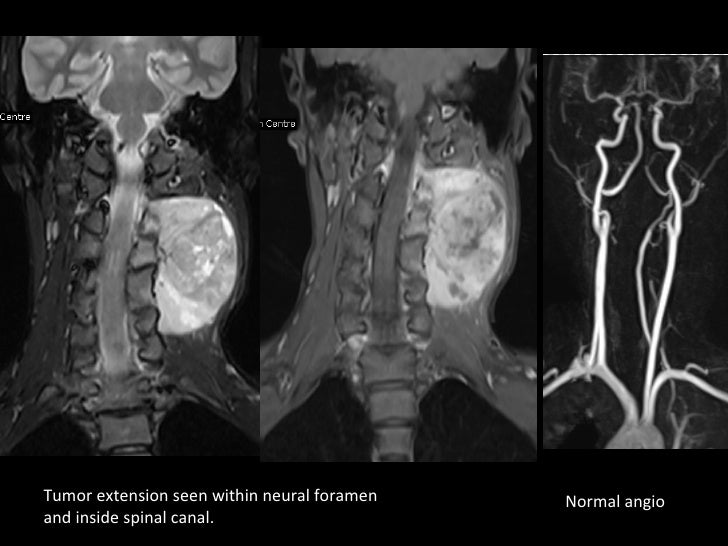

Other neurostimulators may restrict the allowed mri power or scan location, preventing imaging on your. This regularly updated map of the tumor gives the care team an opportunity to tailor the radiation plan. Mris provide a very detailed view, and may help determine whether or not the cancer has spread. Magnetic resonance imaging (mri) scan.